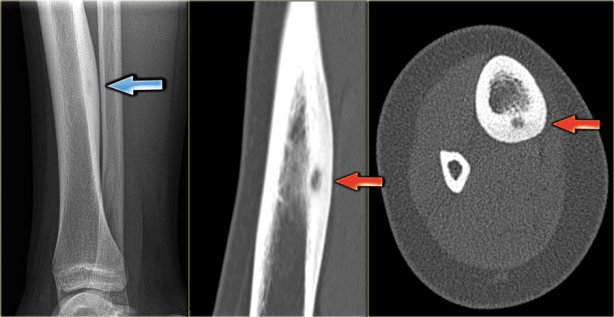

Если заболевание затрагивает детей, может наблюдаться незначительный перекос скелета. Важно отличать эту патологию от злокачественных процессов, особенно если возникает ограничение подвижности в суставе. Рентгенография позволяет легко установить природу опухоли. На снимках доброкачественной остеомы видно, что она имеет однородную структуру, четкие контуры и определенное местоположение.

Опухоль растет медленно, но может прогрессировать при благоприятных условиях. В отличие от обычного рентгена, компьютерная томография предоставляет более точные данные. Остеома может развиваться в течение длительного времени, при этом явные симптомы могут отсутствовать. Временами рост доброкачественного образования может приостанавливаться.

Диагностика остеомы бедренной кости обычно начинается с физического осмотра и сбора анамнеза. Для подтверждения диагноза применяются рентгенография, компьютерная томография (КТ) или магнитно-резонансная томография (МРТ), которые помогают визуализировать опухоль и оценить ее размеры и расположение.